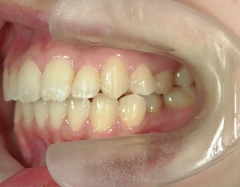

矯正歯科 治療後矯正歯科 プチワイヤー矯正 治療後矯正歯科(プチワイヤー矯正)治療後

矯正歯科 治療後

no.8_8495_治療後_左.jpgno.8_8495_治療後_正面.jpgno.8_8495_治療後_右.jpg